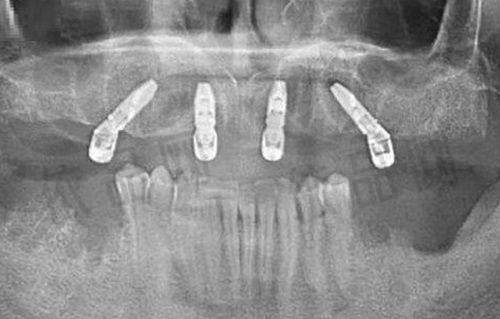

比如,对于正畸患者,医生会根据患者的牙齿畸形程度、年龄、口腔健康状况等因素进行综合评估,然后选择合适的正畸方法,如传统金属托槽矫正、陶瓷半隐形牙套等。对于口腔修复患者,也会根据牙齿缺失的数量、位置、患者的咀嚼习惯等因素,选择合适的修复方式,如种植牙、烤瓷牙等。